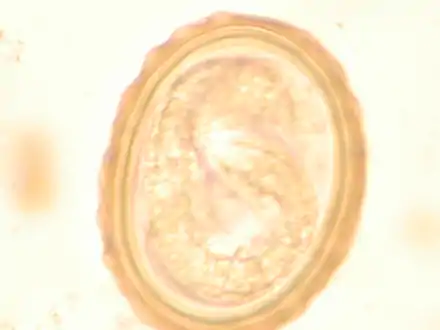

The larva of Ascaris lumbricoides developing in the egg

Ascaris egg, incubation process: The Ascaris egg incubation process consists of placing the egg in a controlled environment, at 26 °C during 28 days, in acidic conditions. This process allows for the evaluation of an egg to determine if it is viable or not.

Most diagnoses are made by identifying the appearance of the worm or eggs in feces. Due to the large quantity of eggs laid, diagnosis can generally be made using only one or two fecal smears.[30] The diagnosis is usually incidental when the host passes a worm in the stool or vomit. The eggs can be seen in a smear of fresh feces examined on a glass slide under a microscope and there are various techniques to concentrate them first or increase their visibility, such as the ether sedimentation method or the Kato technique. The eggs have a characteristic shape: they are oval with a thick, mamillated shell (covered with rounded mounds or lumps), measuring 35-50 micrometer in diameter and 40–70 in length. During pulmonary disease, larvae may be found in fluids aspirated from the lungs. White blood cell counts may demonstrate peripheral eosinophilia; this is common in many parasitic infections and is not specific to ascariasis. On X-ray, 15–35 cm long filling defects, sometimes with whirled appearance (bolus of worms).